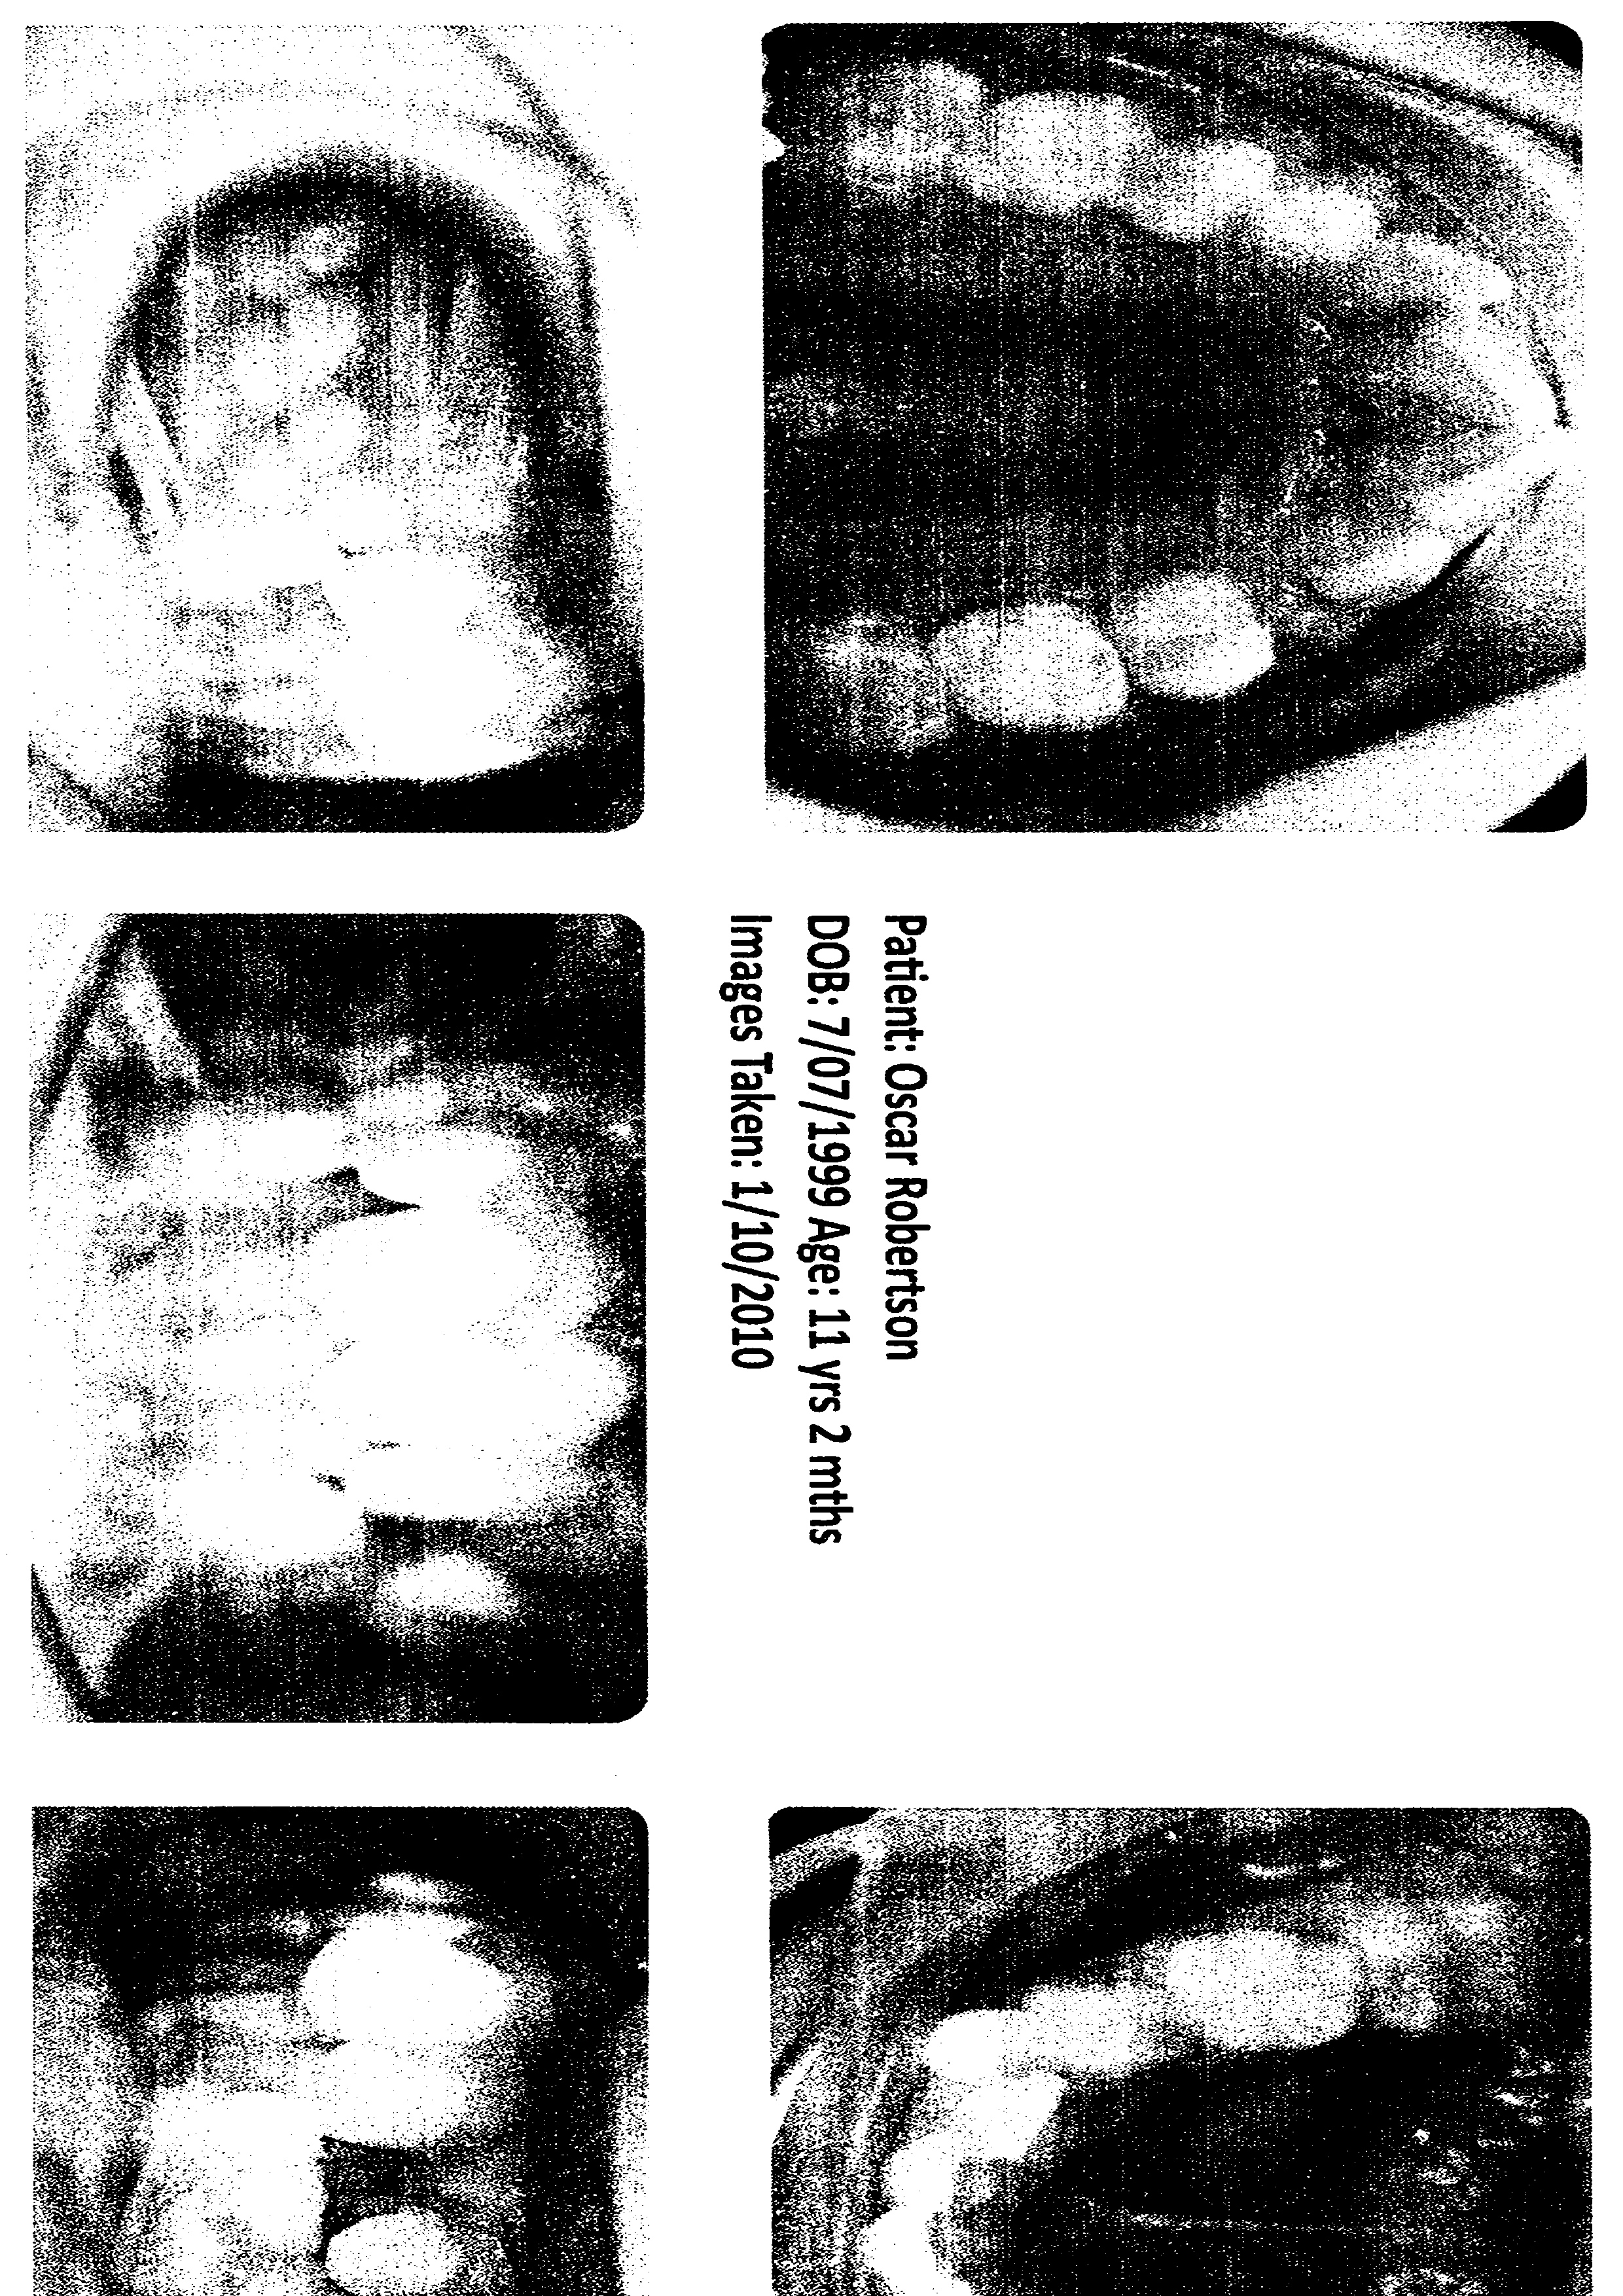

Medical Wrap, Moon Boot, House Paint, Car Mats, Wetsuit, Projection, Casts, Video Work Forensics investigates trauma both physical and mental and how the two might interact through objectivity.